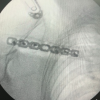

The patient in beach-chair positioned on a radiolucent table with a small bolster beneath the scapula to extend the shoulder. Through a 3 cm anterolateral incision, the deltoid was gently split and the cuff divided in line with its fibers. The entry point was made at the apex of the humeral head just medial to the greater tuberosity, under fluoroscopic control (Fig. 2).

Figure 2: Entry was made at the apex of the humeral head just medial to the

greater tuberosity.

Reaming was carried out slowly and with low torque, to minimize the risk of cortical blowout in fragile bone. A nail of suitable length and diameter was introduced and its proximal end sunk flush with the articular surface, preventing impingement. Proximal fixation was secured with two divergent locking screws (Fig. 3). At the distal end, screws were placed in a single plane, a conscious choice to balance stability against the risk of excessive cortical perforation (Fig. 3).

Figure 3: C-arm images showing the proximal and distal locking.